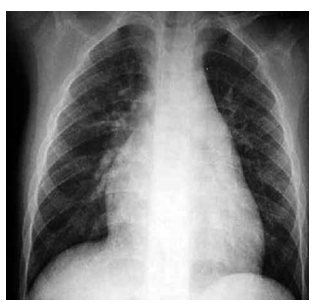

Homem, 35 anos, apresenta os seguintes achados: ventrículo direito palpável, sopro sistólico em borda esternal esquerda alta e desdobramento fixo de segunda bulha. Eletrocardiograma: bloqueio de ramo direito. A radiografia de tórax está ilustrada a seguir.

enunciado 505629-1

O diagnóstico é compatível com